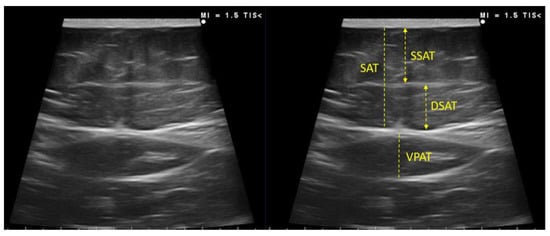

Adipose Tissue Ultrasound Assessment

| Leg | ADIPOSE TISSUE ASSESSMENT | ||||

| Subcutaneous Adipose tissue | 0.76 (0.50–1.49) | 0.71 (0.47–0.83) | 1.66 (1.21–1.80) | 0.007 | |

| Abdomen | Total subcutaneous adipose tissue | 1.80 (1.30–2.60) | 1.65 (1.02–2.35) | 2.98 (1.75–3.72) | 0.008 |

| Superficial subcutaneous adipose tissue | 0.84 (0.57–1.27) | 0.75 (0.42–0.92) | 1.52 (0.99–2.09) | 0.002 | |

| Visceral preperitoneal adipose tissue | 0.70 (0.42–0.87) | 0.70 (0.43–0.86) | 0.69 (0.38–0.90) | 0.917 |